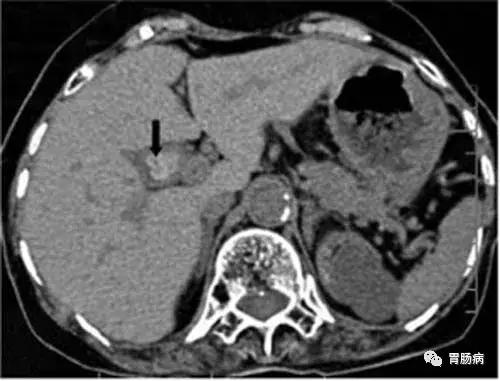

胆囊息肉是胆囊壁向腔内呈息肉样突起的一类病变的总称,包括肿瘤性息肉和非肿瘤性息肉,一般症状轻微,甚至无症状。目前胆囊息肉的病因尚不清楚,长期饮酒,高脂饮食,不吃早餐、压力大、熬夜及生活不规律者,容易得胆囊息肉。胆囊息肉以良性息肉更为多见,但也要预防癌变。

一旦发现就要定期复查,如果符合以下手术指征,建议尽早手术治疗。如胆囊单发息肉直径超过1厘米以上,蒂粗大者,尤其是基底宽,位于胆囊颈部,年龄超过50岁;胆囊多发息肉合并胆囊结石且有症状;胆囊息肉直径小于5毫米,无症状,要每3~6个月随访,迅速增大或症状明显等。